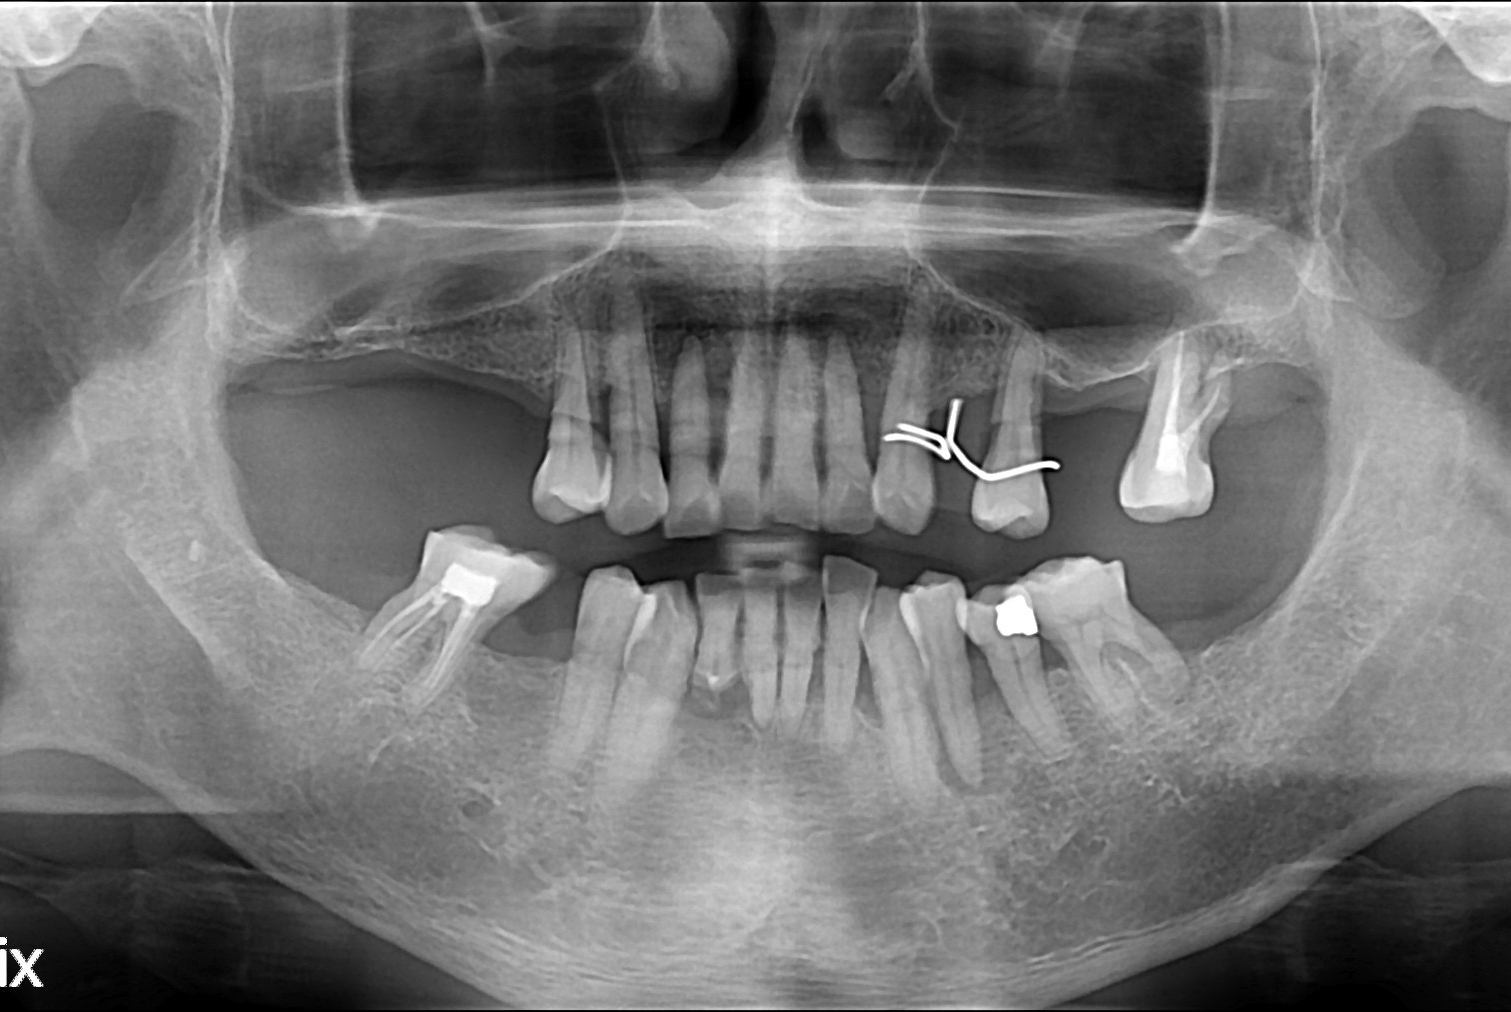

치료전 : 2017-04-21

세종치과는 많은 환자와 다양한 케이스를 바탕으로 항상 편안한 임플란트 수술을 제공하고자 노력하고,

오래동안 튼튼히 쓸 수 있는 임플란트 수술을 가장 큰 목표로 삼고 있습니다